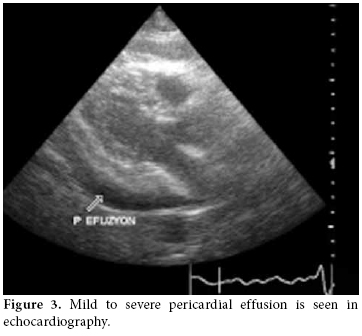

A 47-year-old female patient was admitted to the Yüzüncü Yıl University Faculty of Medicine cardiology clinic with complaints of shortness of breath and palpitations in August 2009. Medium to severe pericardial effusion was detected in an echocardiography examination. Suspecting cardiac tamponade, fluid was drained immediately and in the screening for pericardial effusion, leukocytosis (7200 leukosytes per mm. cub.) was determined. With the diagnosis of pericarditis, ceftriaxone and ciprofloxacin were started. However, no bacterial reproduction was seen in the patient᾿s pericardial fluid or blood cultures. This appeared to be on account of pericarditis due to rheumatoid arthritis. The patient was conscious and cooperative. She had complaints of widespread joint pain, chest pain, shortness of breath, and palpitations. Three weeks after starting sulphasalazine treatment for fever, the patient developed a swollen nose and cheeks along with erythema on her back. These findings were followed by increased skin complaints when exposed to sunshine. Shortness of breath and palpitations developed afterward. An examination revealed pain, swelling, and increased temperature in the carpometacarpal and metacarpophalangeal joints along with a limitation of motion in the left knee. Ulnar deviation and swan-neck deformity were detected in both hands. Tests revealed a blood pressure of 90/60 mmHg and a cardiac pulse rate of 120/min. and a body core fever of 37 centigrate. In a laboratory examination, the following was discovered: leukocyte count 18000, Hgb: 11.5 g/dl, platelets: 365.000, erythrocyte sedimentation rate (ESR): 34 mm/hour, CRP: 18.5 mg/dl, GGT: 283 U/L (5-31), ALT: 40 U/L (0-31), AST 35 U/L (0-31), LDH: 730 U/L (240-480), RF: 141 IU/mL, and anti-CCP was found to be positive.

In high resolution computed tomography (HRCT) there was linear atelectasis, and fibrotic changes were found which were more pronounced in the upper lobes of both lungs (figure 2). Mild to severe pericardial effusion was seen in echocardiography (ECHO; figure 3). Three days after 20 mg intravenous prednisolone therapy, fluid accumulation was considered to be gradually decreasing in ECHO (figure 4).

In the light of present findings, it was thought to be a lupus-like syndrome due to the use of sulphasalazine. Twenty milligram intravenous prednisolone therapy was started, and sulphasalazine was discontinued. Five days later, the ECHO results were considered normal, and the patient was admitted to the rheumatology service to continue a rheumatology examination.